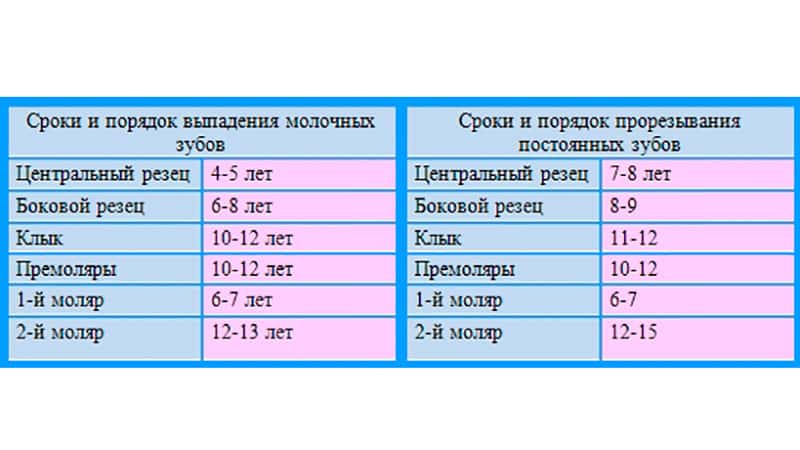

Приблизительная очередность выпадения и смены зубов:

Возраст ребенка Зубы

6 – 7 лет – Нижние, а за потом верхние центральные резцы, первые моляры

7 – 8 лет – Боковые резцы

9 – 10 лет – Первые премоляры

10 -11 лет – Прорезывание клыков, вторых премоляров

11 -13 лет – Вторые моляры

Во сколько лет выпадают молочные зубы у детей? Смена молочных на коренные начинается в среднем с 5-6 лет, но процесс, предшествующий выпадению происходит еще задолго до этого. Начиная с 4-6 лет, у ребенка рядом с молочными зубами прорезываются третьи моляры (самые дальние в зубном ряде, так называемые «шестерки»), которые являются первыми постоянными зубками.

Выпадают они в течение 5-8 лет, начиная с 5-летнего возраста и до достижения ребенком 13 лет. К 14 годам зубной ряд подростка должен состоять из всех коренных зубов.

Молочные зубы у детей: схема выпадения

Выпадение начинается с резцов и далее в том же порядке, что и их прорезывание. В норме выпадать зубки у ребенка должны согласно следующему графику:

- Центральные резцы выпадают к 6-7 годам.

- Вторые резцы начинают выпадать к 7-8 годам.

- Первые моляры выпадают к 10 годам.

- Клыки и вторые моляры к 12 годам также заменяются на постоянные.